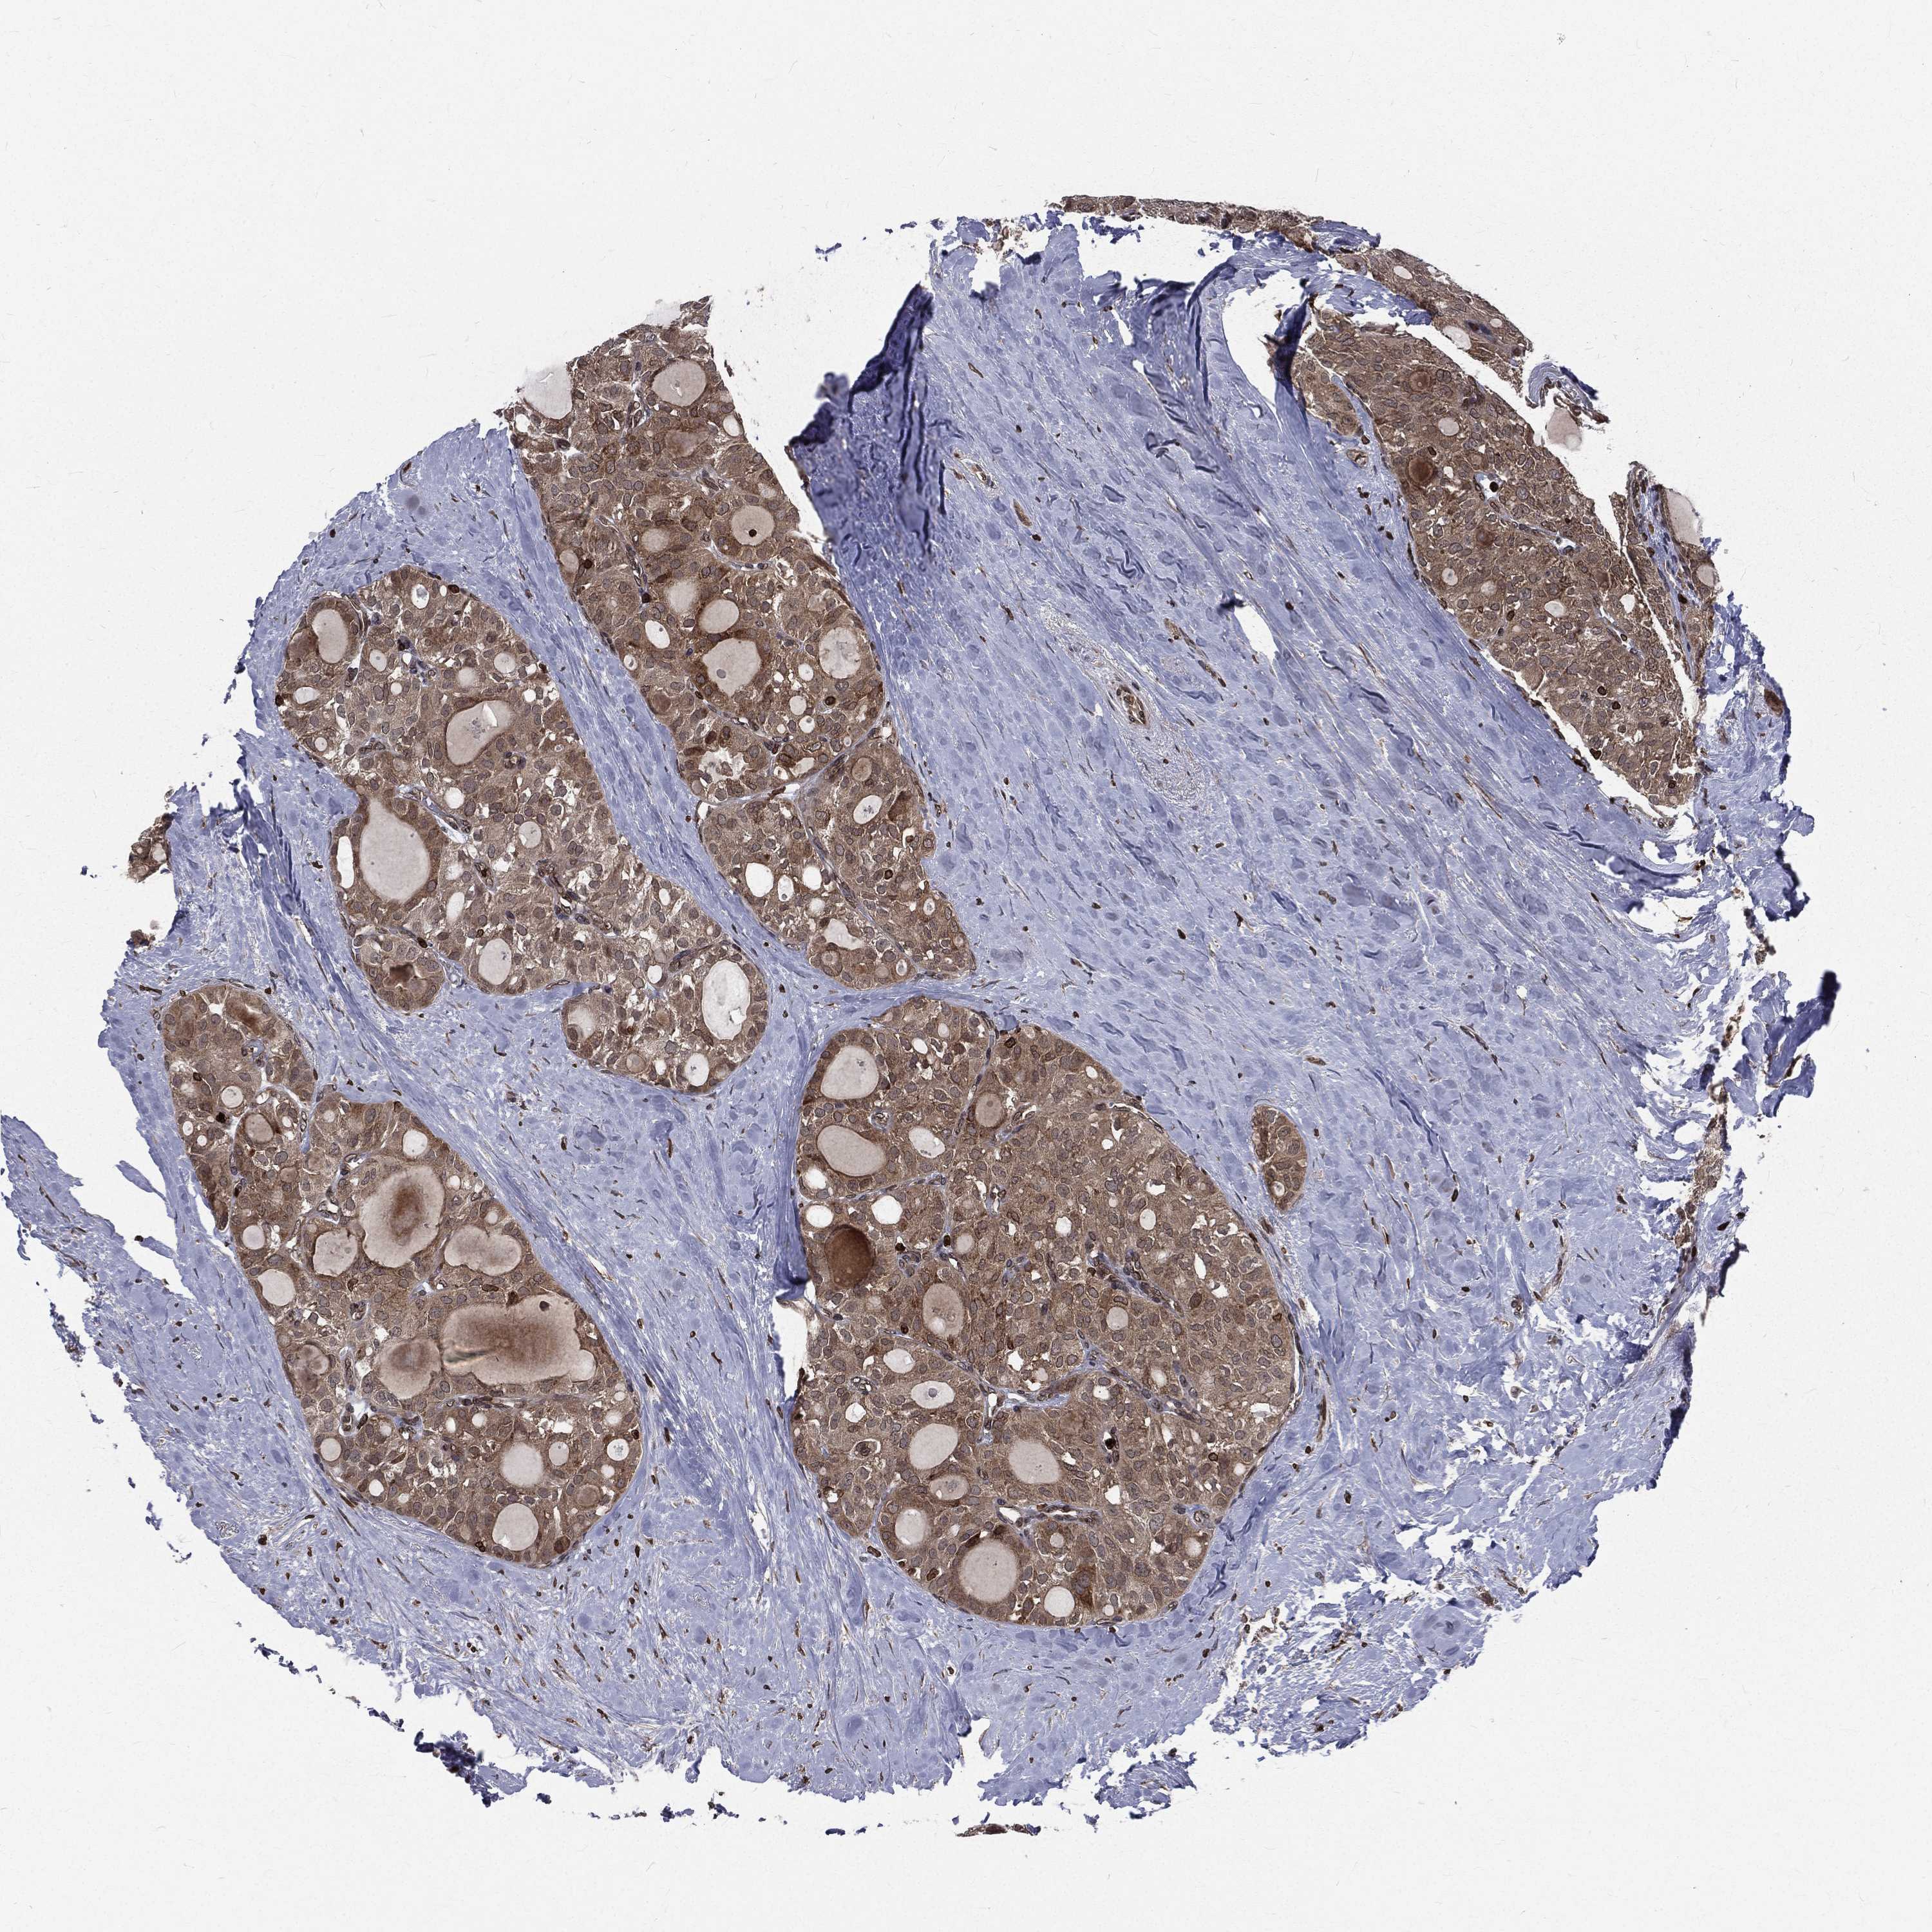

THYROID CANCER - Protein expressioni

A mouse-over function shows sample information and annotation data. Click on an image to view it in a full screen mode. Samples can be filtered based on level of antibody staining by selecting one or several of the following categories: high, medium, low and not detected. The assay and annotation is described here.

Note that samples used for immunohistochemistry by the Human Protein Atlas do not correspond to samples in the TCGA dataset.

Antibody stainingi

Antibody staining in the annotated cell types in the current human tissue is reported as not detected, low, medium, or high, based on conventional immunohistochemistry profiling in selected tissues. This score is based on the combination of the staining intensity and fraction of stained cells.

Each image is clickable and will lead to virtual microscopy that enables deeper exploration of all samples and also displays staining intensity scores, fraction scores and subcellular localization as well as patient and tissue information for each sample.

Antibody HPA049840

Antibody HPA062236

Staining

High

Medium

Low

Not detected

Intensity

Strong

Moderate

Weak

Negative

Quantity

>75%

75%-25%

<25%

None

Location

Nuclear

Cytoplasmic/membranous

Cytoplasmic/membranous,nuclear

Papillary adenocarcinoma, NOS

Follicular adenoma carcinoma, NOS